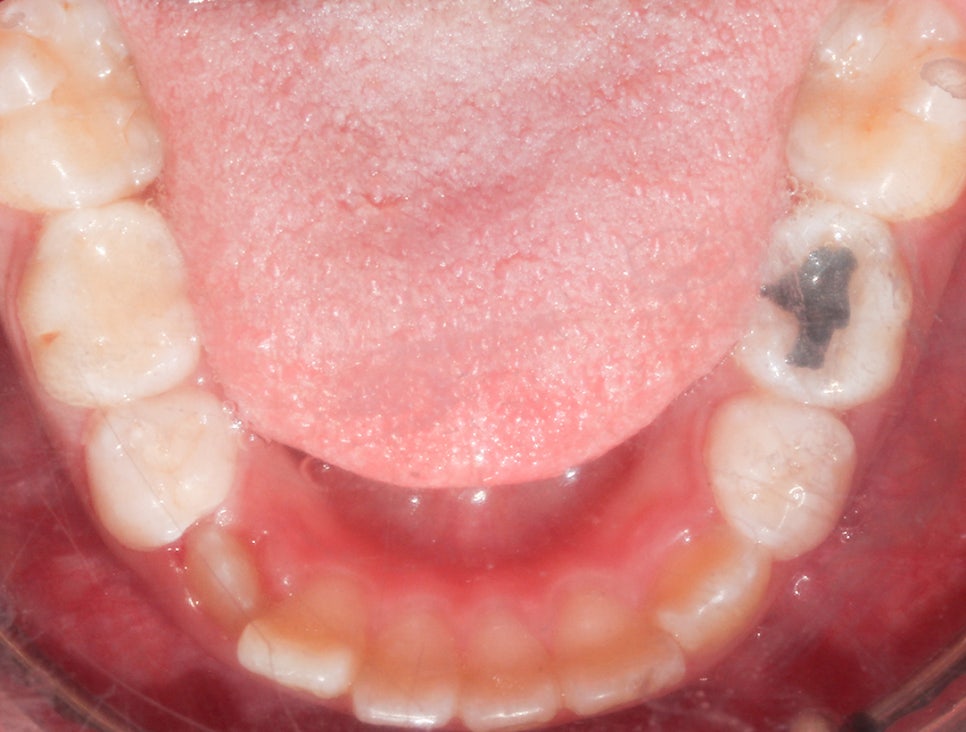

환자분의 상태를 살펴보면

치아가 날 공간이 부족하거나 치아가 나오는 방향에서

앞니가 앞으로 나오고 다른 치아가 기울어지면서

거꾸로 물리는 현상이 발생한 걸로 보여요.

상하악 Clippy-C (클리피씨) 전체 교정

구치부 반대교합은 통상적으로 비발치 교정일 경우에는

1년~1년 반 정도 교정 기간을 생각하고 있었어요-:D